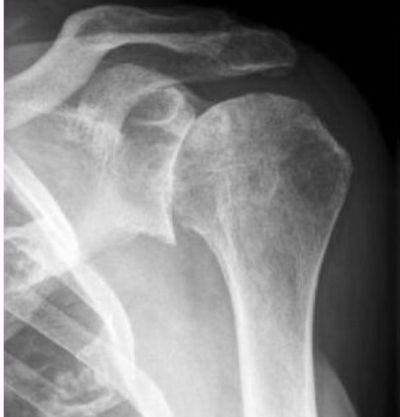

Чтобы понять, какие именно отклонения выявились на снимке, нужно знать, как выглядит снимок после проведения рентгена плечевого сустава в норме. Врач различает потемнения, видит наличие просветов в структуре костной ткани, определяет ее изменения, а также безошибочно находит очаг заболевания. Нормы показателей:

- Контуры костей четкие, ровные. Костная структура не изменена.

- Полное соответствие формы соприкасающихся суставных поверхностей.

- Суставные щели хорошо прослеживаются, не сужены.

- Контуры смежных поверхностей с обеих сторон четкие, ровные. Костных разрастаний не отмечается.

- Костно-дистрофических изменений, а также дистрофических или травматических не выявлено.

- Мягкие ткани не изменены.

Рассматривая пленку, врач оценивает состояние костных структур, суставной щели, хрящи, очертания кортикального слоя и мягкие ткани, окружающие сустав.